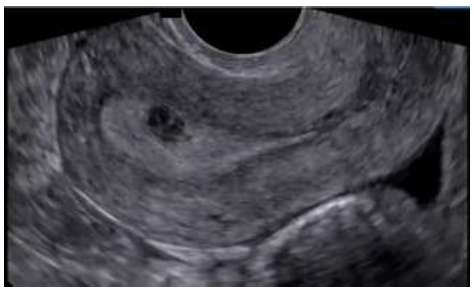

São critérios para diagnóstico de gestação não evolutiva ou não viável: